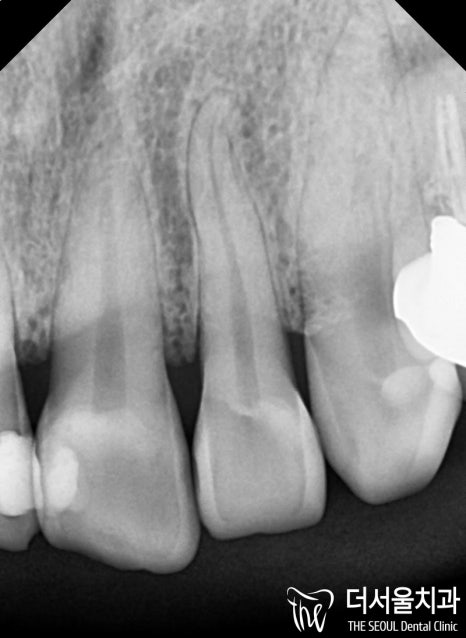

군데군데 거뭇하게 보이는 우식이 관찰되었는데요.

치경부 마모가 나타나 있었기 때문에

이시림도 동반되고 있었습니다.

치아 사이에 나타나 있던 우식!!!!

인접면에 나타난 우식은

겉으로 봤을 때 티가 잘 나지 않기 때문에

조기에 발견하는 것이 쉽지 않습니다.